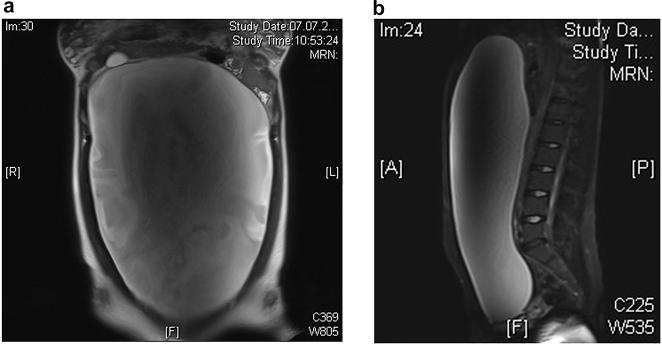

Ovarian lesions are rare but frequent in children. Patients could present with abdominal pain, but ovarian lesions could also be incidentally found on ultrasound. Awareness is required in cases with acute, severe lower abdominal pain, as ovarian torsion could be the cause. Other lesions can be cysts or benign or malignant ovarian tumors. Thus, the aim of this paper is to review typical ovarian lesions according to age, imaging and laboratory findings, and surgical management.

Ovarian lesions in children younger than 2 years of age were typically ovarian cysts, and ovarian tumors were not observed in this age group. In older children over 10 years of age, tumors were more common - with mostly teratoma or other germ cell tumors, followed by epithelial tumors. Moreover, acute or chronic ovarian torsion was observed in all age groups. In general, ovarian tumors were much larger in size than ovarian cysts or twisted ovaries and eventually showed tumor marker expression of AFP or ß-HCG. Simple ovarian cysts or twisted ovaries were smaller in size. Surgery for all ovarian lesions should aim to preserve healthy ovarian tissue by performing partial ovariectomy.